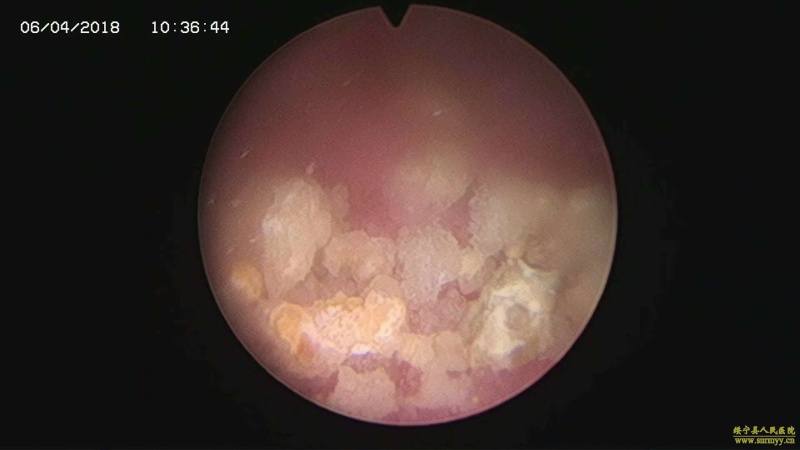

多镜联合治结石 4月6日,处于休假期间,但绥宁县人民医院泌尿外科的医护没有休息,在科主任张华生的带领下,打破常规,挑战高度,成功完成了一台复杂的结石手术。 据悉,患者姓杨,是一位60岁的男性患者,因"间断性左侧腰痛2年,再发伴尿痛2天"入院,经检查后发现患者左肾、左侧输尿管、膀胱内均有多发结石。针对这种结石,传统的手术方法至少需要开3刀,且需分期进行,使得患者痛苦大、治疗周期延长,费用也相应增高。肾结石开刀手术后劳动力会严重散失,即使采用现在流行的微创手术,常规也得分期进行,患者免不了多次手术的痛苦。为进一步减轻患者痛苦,绥宁县人民医院泌尿外科的医师们经过慎重考虑,决定打破常规,制定了多镜联合取石的手术方案。手术在4月6日顺利进行,术中联合膀胱镜、输尿管镜、经皮肾镜进行了长达70分钟的治疗,使得出血量不超过5mL且伤口仅0.5cm,一次性将患者膀胱,左侧输尿管,左肾结石全部取出。术后第五天经复查无任何结石残留,4月13日患者顺利出院。 目前,绥宁县人民医院泌尿外科在微创手术治疗各种尿路结石的技术上,己非常熟练。结石在整个邵阳地区发病率都很高,平常多喝水,每天饮水2000ml以上,调节饮食生活习惯,坚持锻炼可以有效预防结石发生,定期的健康体检也是预防结石的有效措施之一,可以早期发现结石,及时治疗。(图文 付志峰 编辑 谢雅玲) 图为:泌尿外科主任张华生、副主任付志峰进行手术时场景 图为:膀胱结石显象→手术碎石中显像→膀胱结石碎石后显像 图为:输尿管结石显像→输尿管结石碎石后显像 图为:肾结石显像→取出的肾结石标本 图为:术中建立穿刺通道 图为:术后留置的引流管 图为:术后伤口情况 |